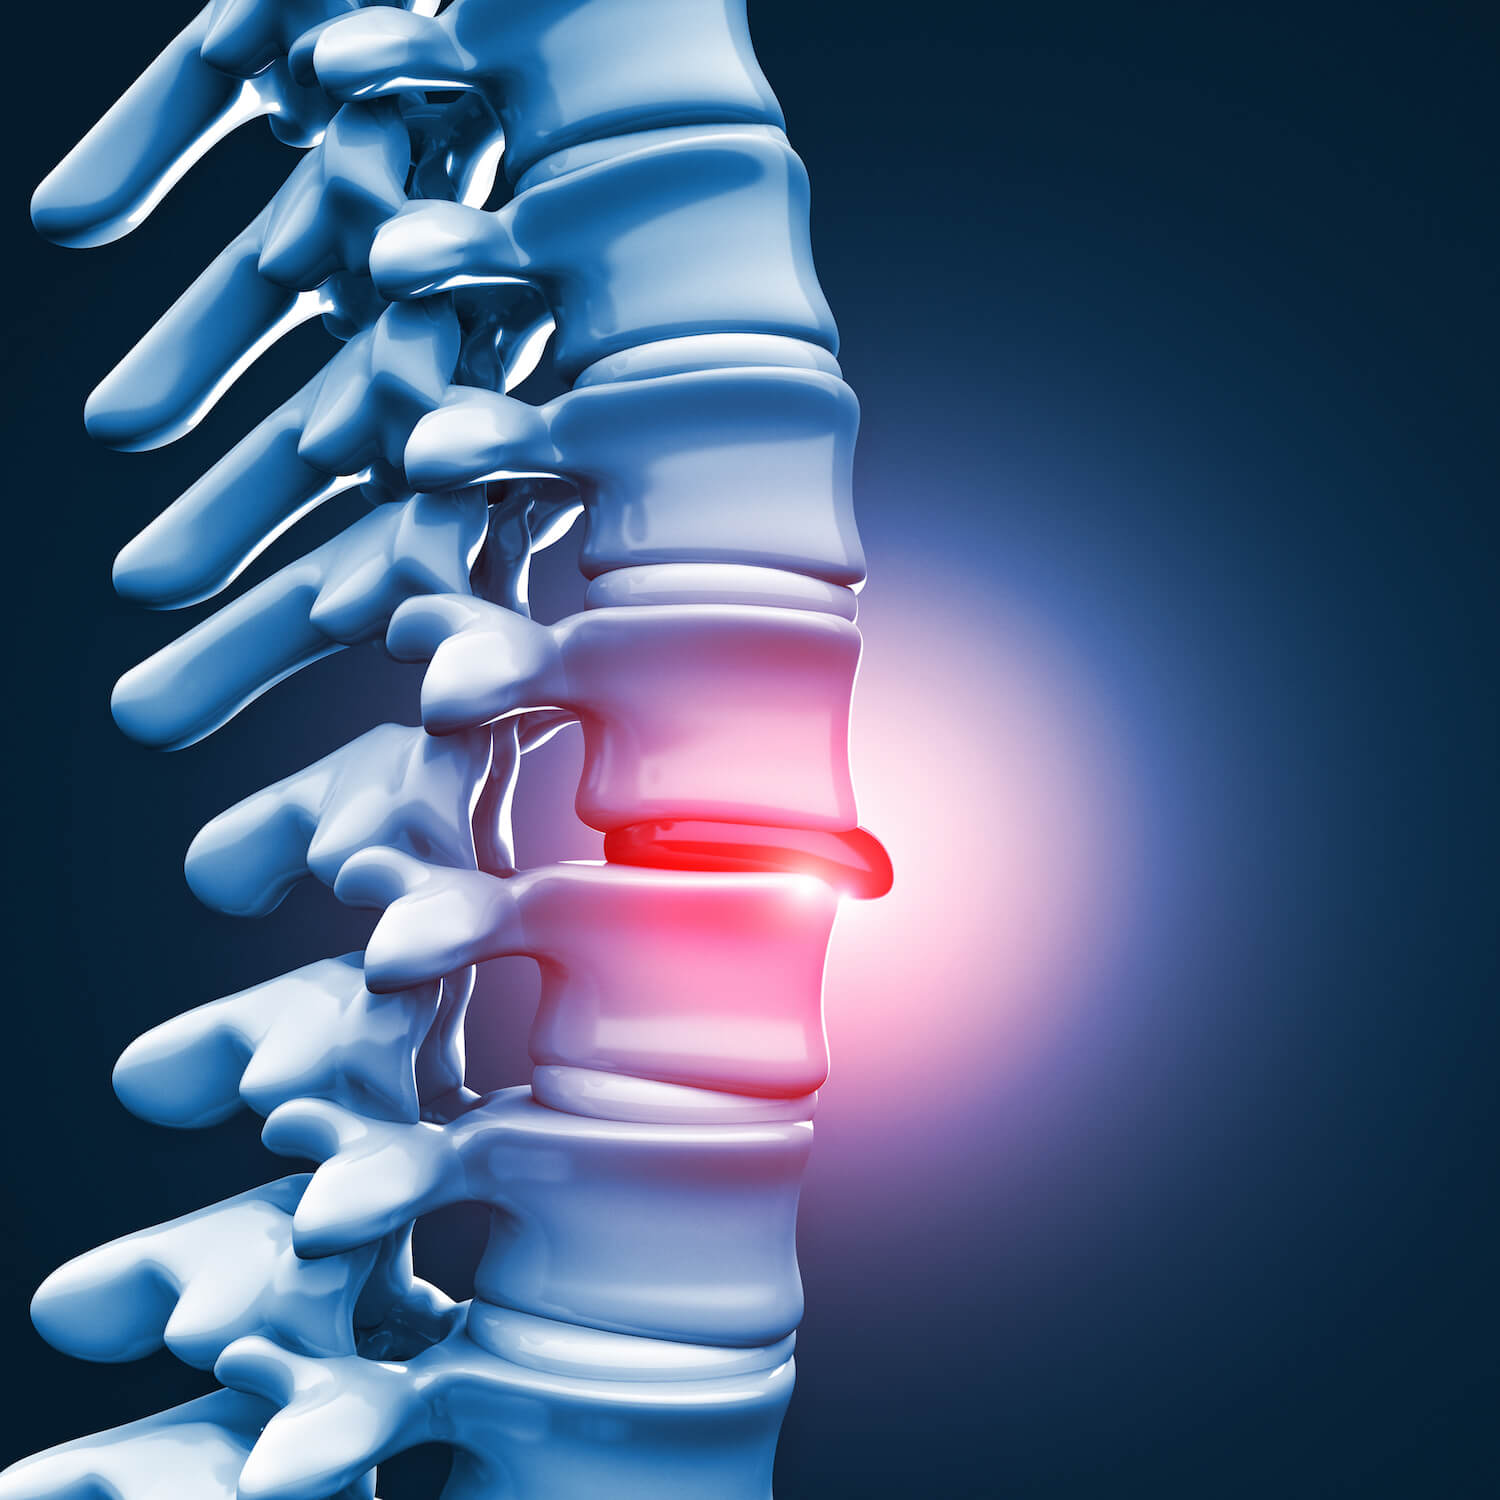

Spinal Cord Under Pressure Of Bulging Disc Stock Illustration …

Sciatica, Spinal Stenosis, Bulging Disc & Other Disc Conditions

Bulging Discs | Nevada Pain – Las Vegas, Summerlin, Henderson